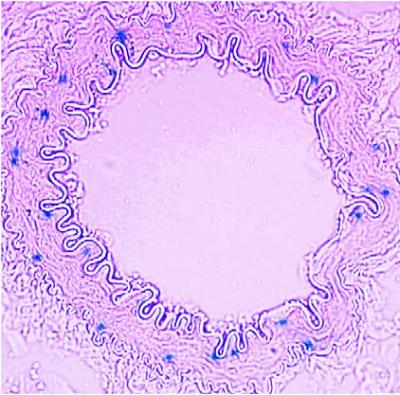

Prostaglandin F2-alpha receptor expression is depicted in blue in a renal artery. Credit: Ying Yu, PhD, and Garret FitzGerald, MD, University of Pennsylvania School of Medicine

The team found that the PG F2-alpha receptor is expressed in the smooth muscle surrounding arteries in the kidneys. However, it was absent in the muscle surrounding the aorta, in the atherosclerotic lesions of mice with their PG F2-alphareceptors knocked out, as well as in the macrophages that inhabit those lesions. Importantly, these atherosclerotic lesions were smaller and less abundant in mice that had both the low-density lipoprotein and PG F2-alpha receptors knocked out, as was macrophage infiltration and inflammatory cytokine production, both of which are indicators of the inflammatory response that marks these plaques.